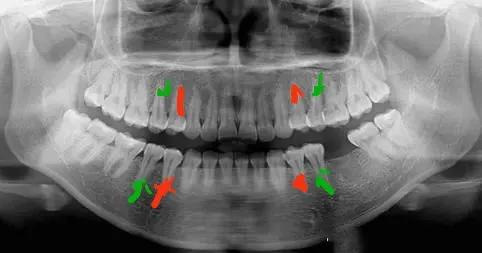

4號牙指第一前磨牙,又叫第一雙尖牙,是從門牙往后數(shù)的第四顆牙齒,在它后面的叫做第二前磨牙,稱為5號牙。正畸拔牙也是有一定規(guī)律的,通常情況下,第一前磨牙(4號牙)是拔牙矯正中_常拔除的對象。

當(dāng)牙列擁擠程度或牙弓前突相對小時,會選擇拔第二前磨牙(5號牙),前磨牙的咀嚼效率低,影響_小,拔除前磨牙不容易引起患者面型坍塌和美觀。當(dāng)然也有其他情況的存在,需要根據(jù)患者情況具體判斷。

另外,正畸拔牙大部分是左右對稱拔除,可防止中線偏移,保證美觀與咬合關(guān)系正常。

紅色為4號牙,綠色為5號牙